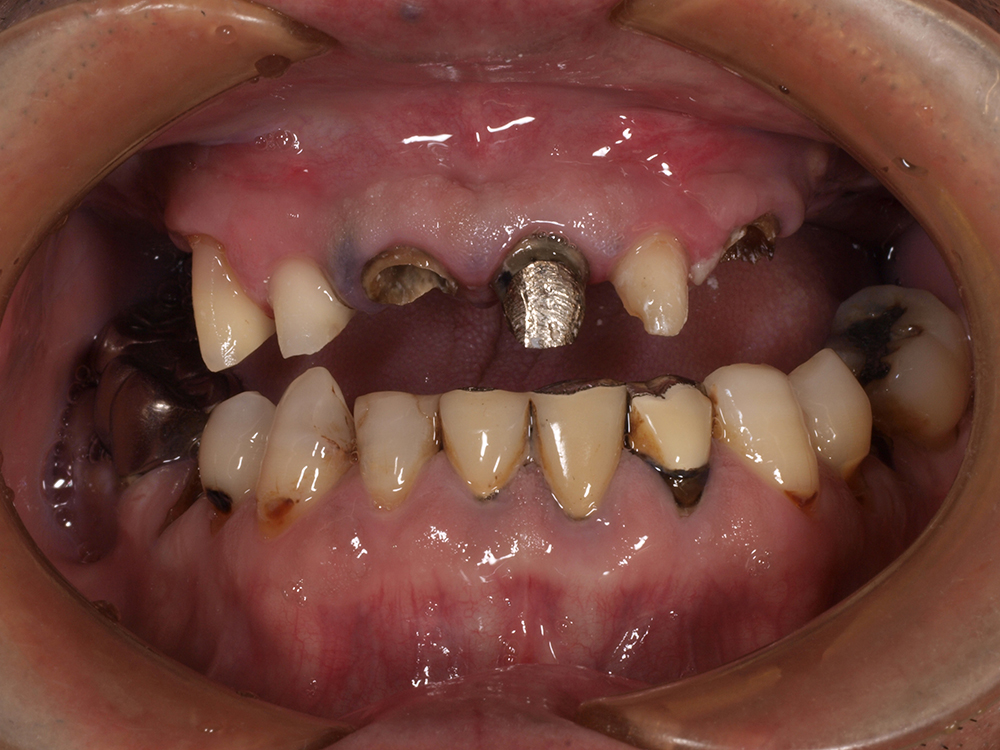

53歳 男性

- 主訴

- 全然噛めない。上の歯が取れてきた

- 処置内容

- 上顎:8本 下顎:2本

- 治療費用

- 上顎:約320万円(税込)、下顎:約160万円(税込)

- 治療期間

-

上顎:1年(仮歯まで8か月)

下顎:8か月(仮歯まで5か月)

- リスク

- 上部構造物、仮歯の破折、術後の腫れ(3日)、人工歯根脱落リスクがあります